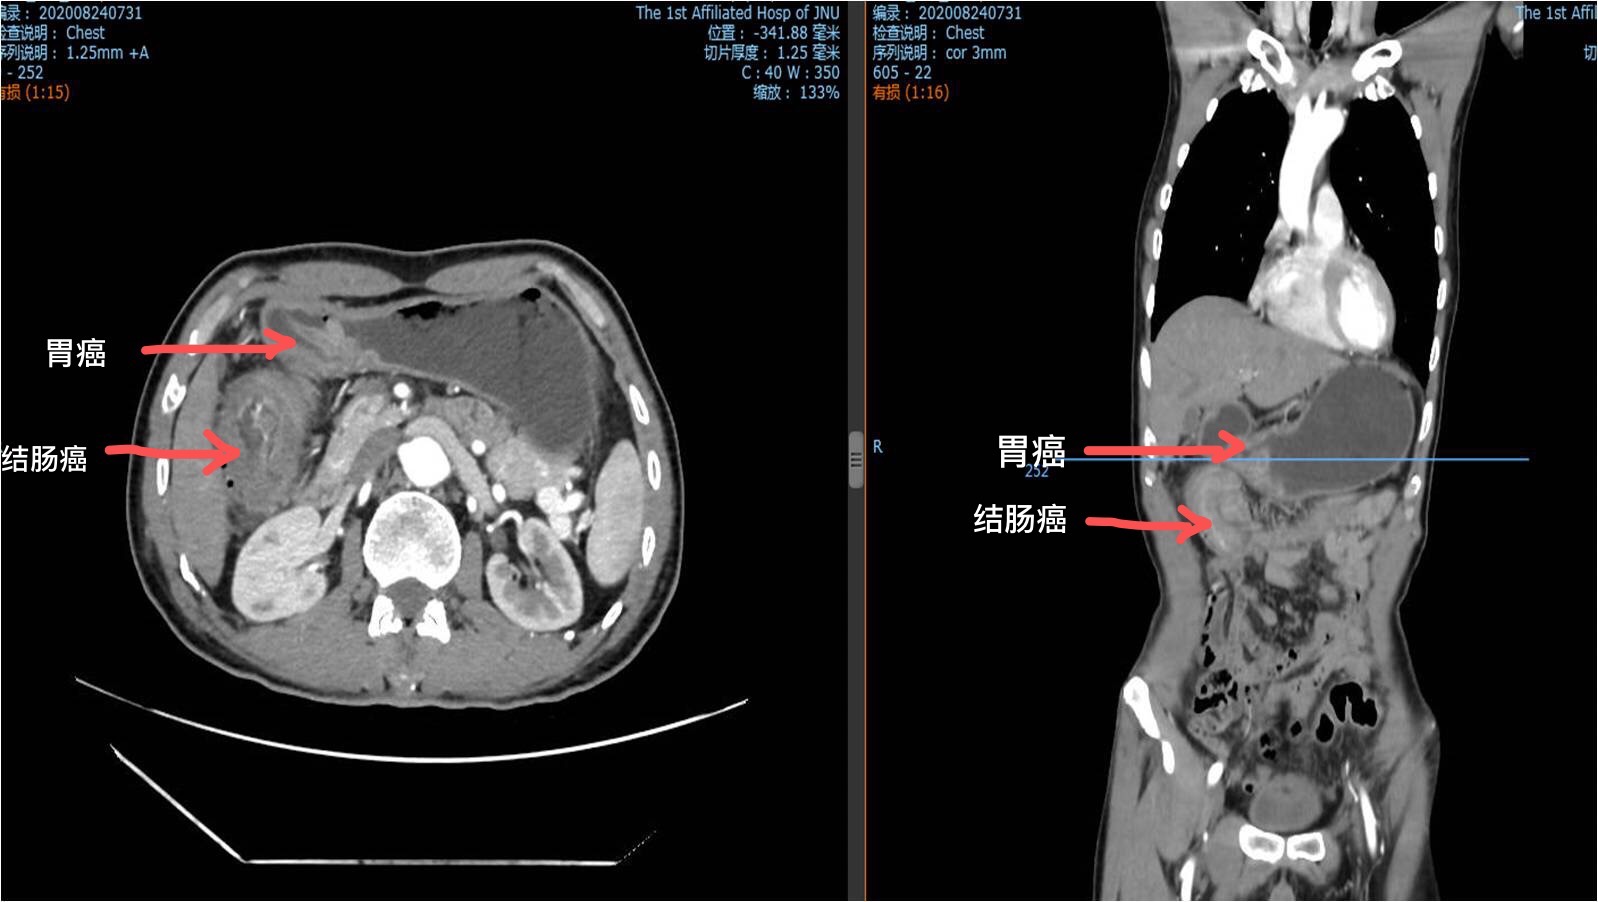

69岁的梁伯(化名)来自粤北山区,平时非常喜欢吃腌制食物。三个月前,他开始出现大便习惯改变,便血且有黏液,伴右中腹部隐痛不适。在家人的陪伴下到当地医院就诊,肠镜检查显示升结肠有个拳头那么大的肿瘤,阻塞肠腔,提示升结肠癌,立即转诊到暨南大学附属第一医院治疗。

接诊医生、暨南大学附属第一医院胃肠外科主任医师杨景哥马上安排给梁伯做了全面检查,做胃镜时发现梁伯的胃窦部也有个肿瘤,病理提示中分化腺癌!询问病史发现,梁伯平时也觉得胃部有点不舒服,上腹部经常腹胀,但由于不影响生活,梁伯也就没有太在意,也没有去做检查。

一次微创手术切除两种肿瘤